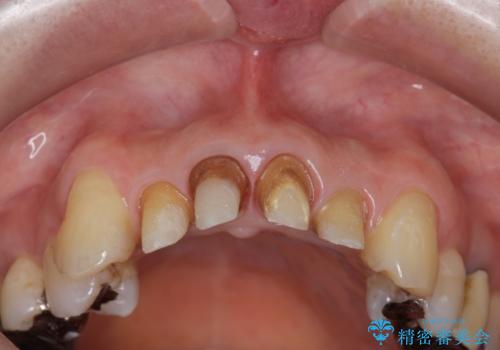

- 20年前に治療した前歯の劣化・審美障害の改善を求めて来院されました。

クラウンを除去し審美的なジルコニアクラウンによる補綴の再作製計画を立案します。

- 52万円(仮歯×4・ファイバーコア×4・ジルコニアクラウン×4)費用は治療当時の料金となります